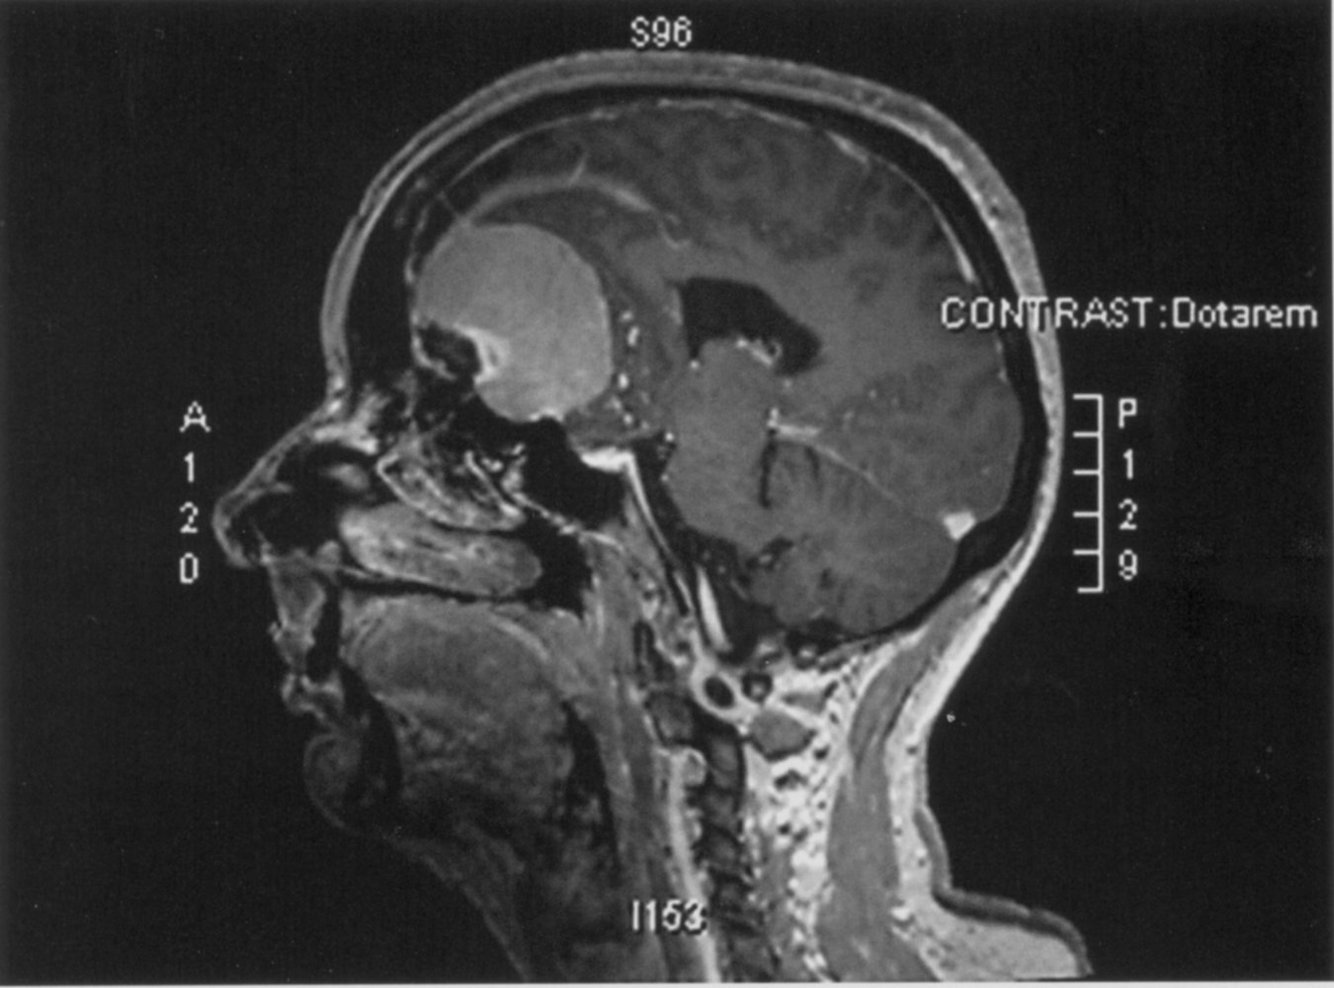

What is going on in this image?

Medulloblastoma

Note the solid and cystic components (cystic is the inferior-most) and the location

Commonly in kids. They present with truncal ataxia, generalized cerebellar abnormalities, and double vision/oculomotor abnormalities